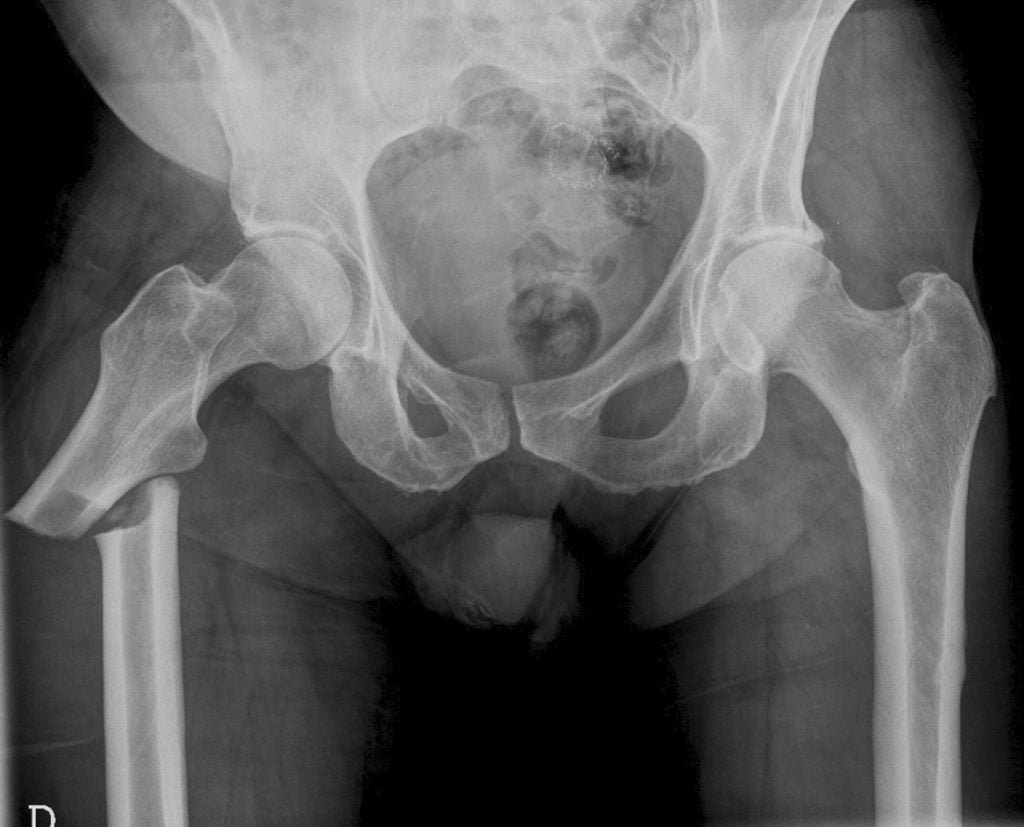

На поздних стадиях остеопороз диагностируется с помощью обычной рентгенографии. Опытный ортопед может легко обнаружить характерные для болезни изменения на рентгенограммах. К сожалению, такое обследование малоинформативно при начальных изменениях в костях.

Прочность костной ткани – это главный показатель, предопределяющий появление переломов. Риск напрямую зависит от МПК в области позвоночника и шейки бедра. Чем ниже минеральная плотность, тем меньшей травмирующей силы достаточно для нарушения целостности кости.

У пожилых людей падения с высоты роста в 87% случаев приводят к переломам проксимального отдела бедра. Также бытовые травмы могут вызывать повреждения позвонков, дистальной трети предплечья и пятки.